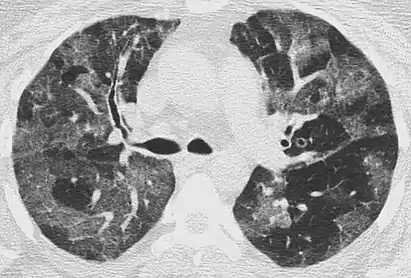

CT image showing patchy areas of ground-glass opacities representing pulmonary edema.

The diffuse pattern typically refers to GGOs in multiple lobes of one or both lungs. Broadly, a diffuse pattern of GGO can be caused by displacement of air with fluid, inflammatory debris, or fibrosis. Cardiogenic pulmonary edema and ARDS are common causes of a fluid-filled lung. Diffuse alveolar hemorrhage is a rarer cause of diffuse GGO seen in some types of vasculitis, autoimmune conditions, and bleeding disorders.[6]